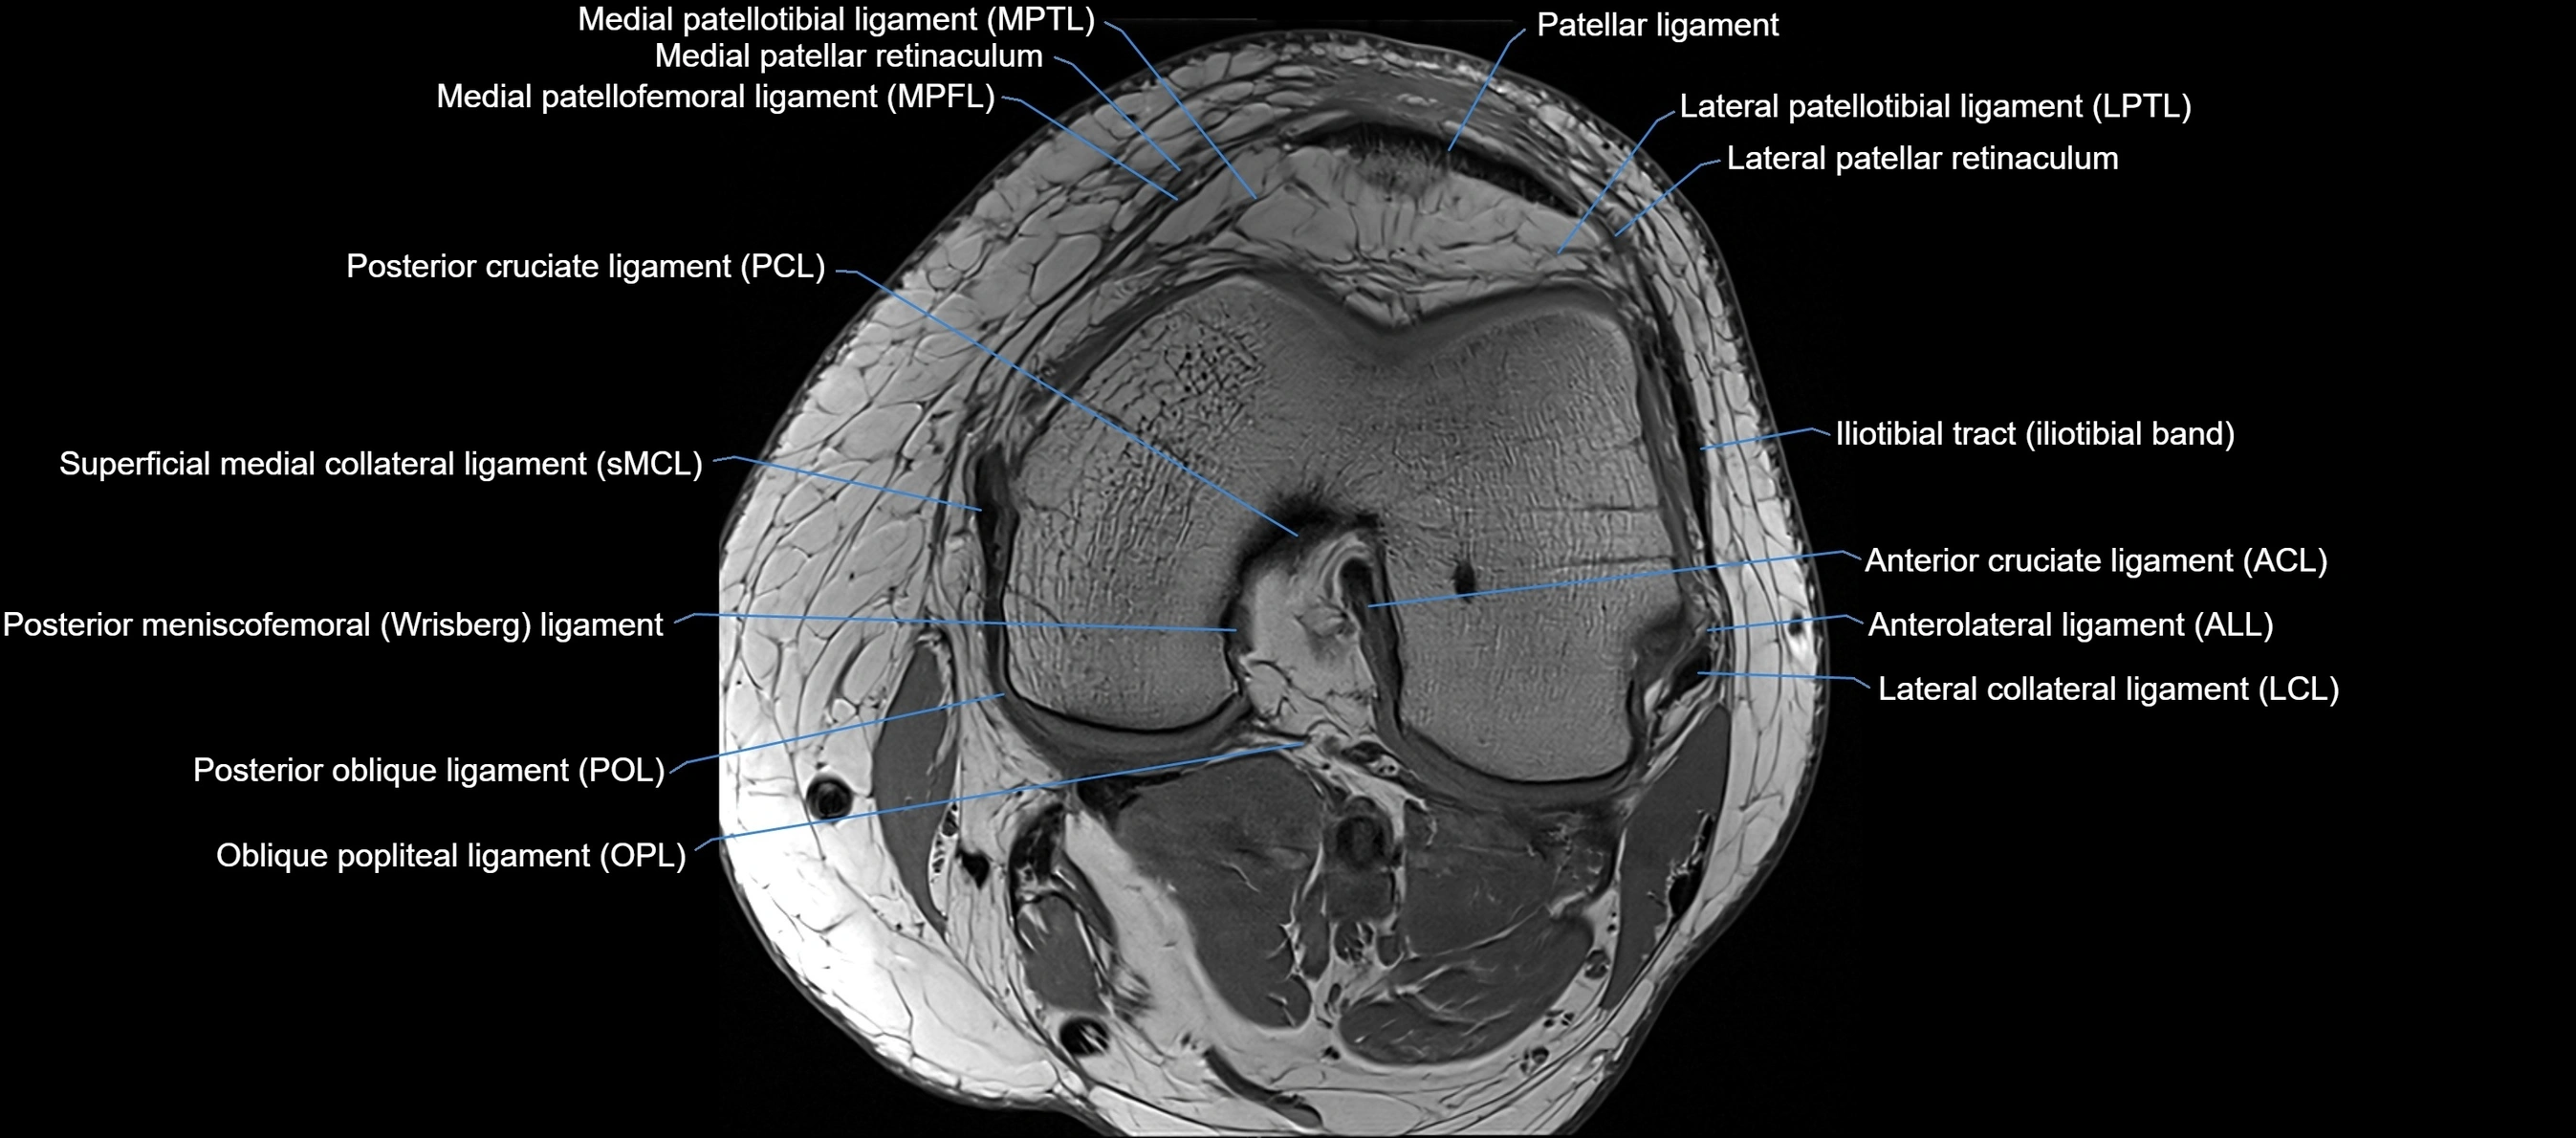

MRI images

image